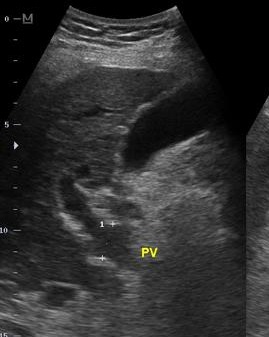

Image echographique de la

cirrhose du foie au debut

. Foie est en hypoechogene a bord irregulier , veine porte

est dilate |